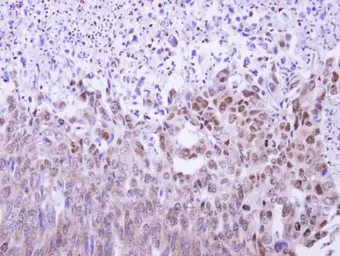

Anti-MAF1 antibody used in IHC (Paraffin sections) (IHC-P). GTX106776

GTX106776 IHC-P Image

MAF1 antibody detects MAF1 protein at nucleus on human endometrial carcinoma by immunohistochemical analysis.

Sample: Paraffin-embedded human endometrial carcinoma.

MAF1 antibody (GTX106776) dilution: 1:500.

Antigen Retrieval: Trilogy™ (EDTA based, pH 8.0) buffer, 15min